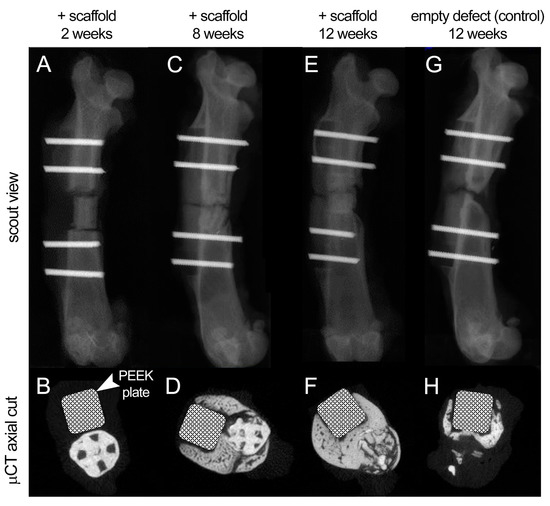

3.6. In Vivo Regenerative Capacity of Bioprinted Damage-Specific HB Constructs